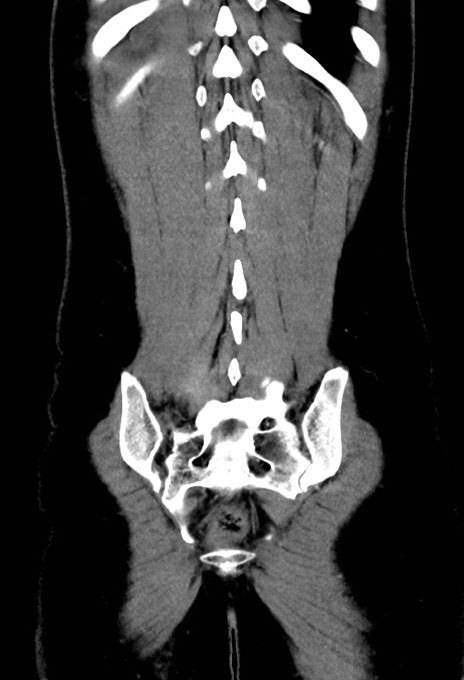

症例17(冠状断像)

【症例】20歳代女性

【主訴】嘔吐、下腹部痛

【現病歴】昨日夕食後に嘔吐し下腹部痛が出現。本日になっても嘔吐持続し改善しないため来院。

【身体所見】意識清明、BT 37.2℃、BP 108/67mmHg、腹部:平坦、やや硬、下腹部正中から右にかけて圧痛あり、反跳痛軽度あり、tapping pain(+)。

【データ】WBC 13600、CRP 14.94